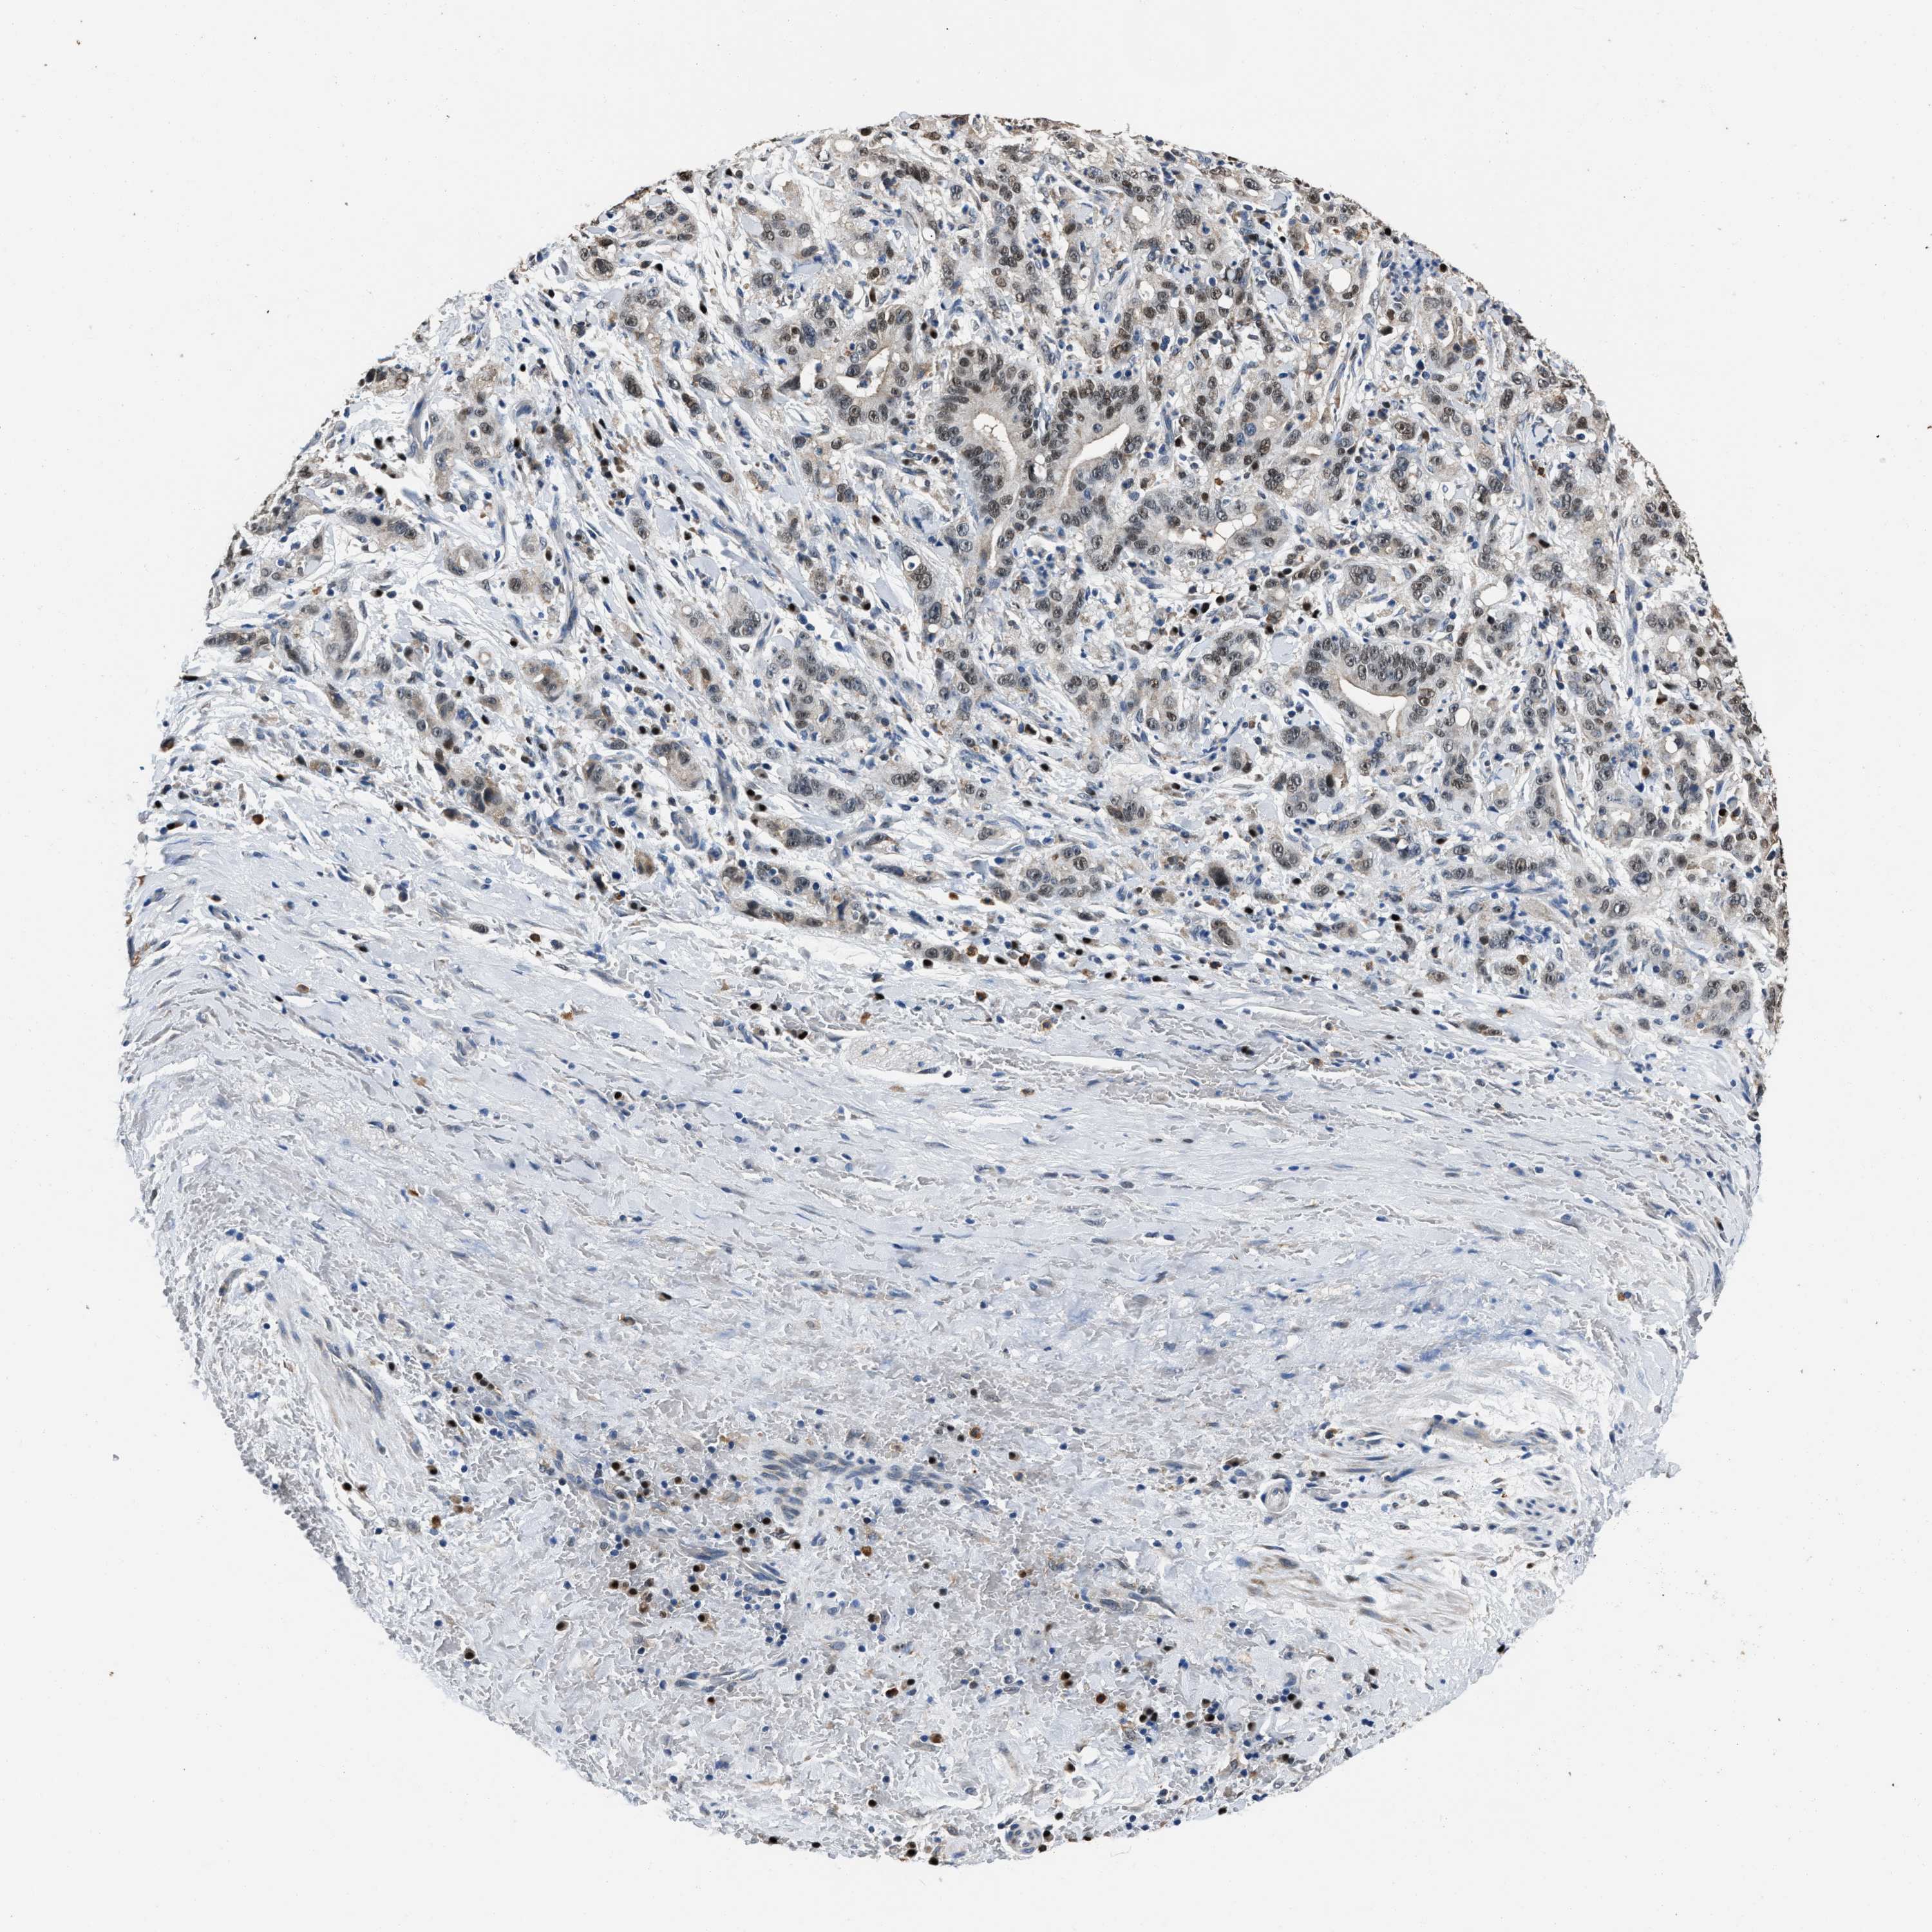

LIVER CANCER - Protein expressioni

A mouse-over function shows sample information and annotation data. Click on an image to view it in a full screen mode. Samples can be filtered based on level of antibody staining by selecting one or several of the following categories: high, medium, low and not detected. The assay and annotation is described here.

Note that samples used for immunohistochemistry by the Human Protein Atlas do not correspond to samples in the TCGA dataset.

Antibody stainingi

Antibody staining in the annotated cell types in the current human tissue is reported as not detected, low, medium, or high, based on conventional immunohistochemistry profiling in selected tissues. This score is based on the combination of the staining intensity and fraction of stained cells.

Each image is clickable and will lead to virtual microscopy that enables deeper exploration of all samples and also displays staining intensity scores, fraction scores and subcellular localization as well as patient and tissue information for each sample.

Antibody HPA020536

Staining

High

Medium

Low

Not detected

Intensity

Strong

Moderate

Weak

Negative

Quantity

>75%

75%-25%

<25%

None

Location

Nuclear

Cytoplasmic/membranous

Cytoplasmic/membranous,nuclear

Cholangiocarcinoma

Carcinoma, Hepatocellular, NOS